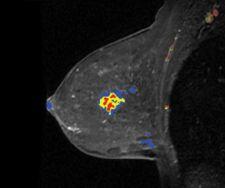

Confirma’s next-generation product for breast MRI includes a new customizable BI-RADS-centric user interface that accommodates a variety of user experience levels. Additional CADstream enhancements include improved 3D renderings and tools for morphology reporting.

The next generation of CADstream for breast MRI enhancements will include a customizable BI-RADS-centric user interface and improved volume summaries and morphology reporting tools. Additionally, the Company will debut the Access Breast Coil with high quality diagnostic capability, flexible interventional access and optimized patient comfort.